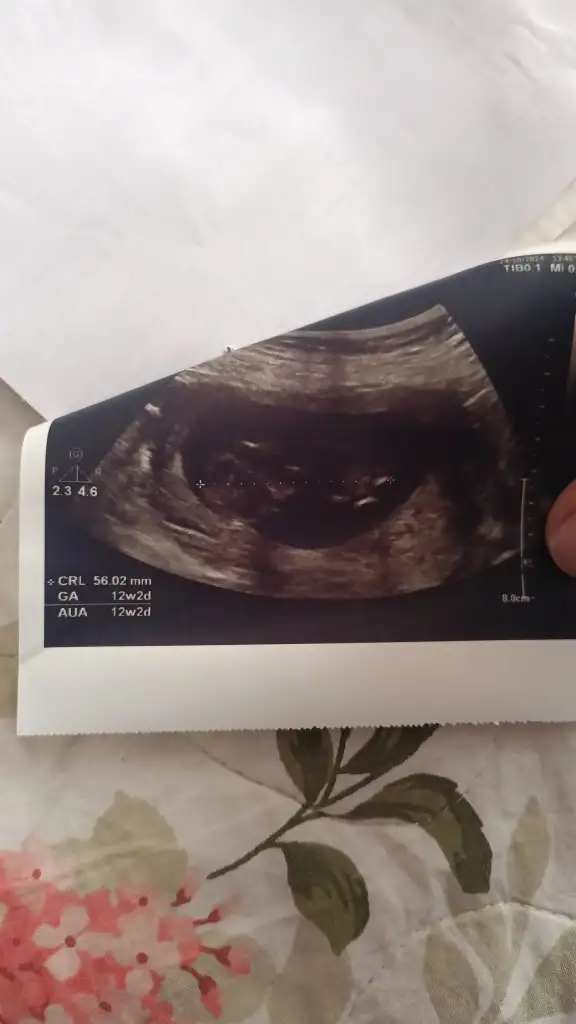

5 ve 14. haftaya kadar olan ultrason fotolarınızı paylaşın. Vajinadan mı yoksa karından mı çekildiğini ve kaç haftalık olduğunu da mutlaka belirtin.